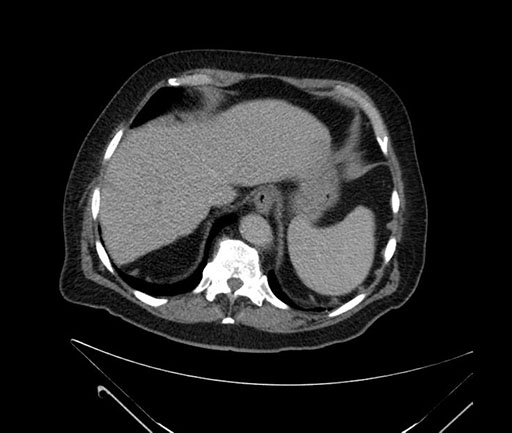

Whipple (pancreaticoduodenectomy) [case 7]

Axial - 3 months prior

Imaging analysis

Based on your CT findings, which issue(s) would give reason for "planned slowing down moment(s)" in this case?

Considering a standard Whipple procedure, what step(s) of the operation would you do differently in this case?